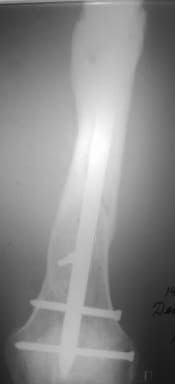

При невозможности или чрезмерной травматичности одномоментного восстановления длины можно пойти двухэтапно (аппарат, потом гвоздь). Похожий пример см. тут. Прошло уже года полтора после остеосинтеза. Может, коллега Зырянов покажет годичный результат, если есть?

Отправитель: Сергей Зырянов 16 Декабрь 2005, 08:20

Александр Николаевич, к сожалению больной не является на контрольные осмотры. Я последний раз видел больного, когда прошло 7 месяцев после операции БОС. У него все хорошо. Каких либо жалоб и ограничений в нагрузке нет. Высылаю снимки до операции и последние снимки.